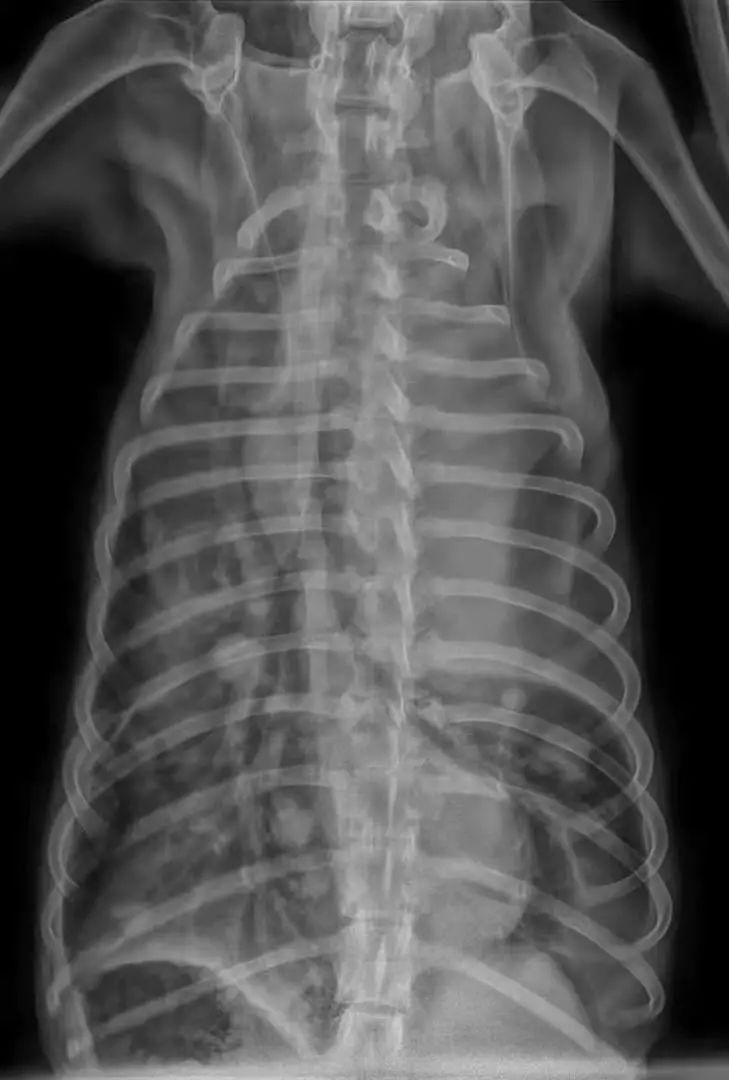

家长说动物干呕了二十天左右,不爱吃饭来就诊,但实际症状为咳嗽,消瘦,当触诊到腹部一个拳头大乳腺肿瘤的时候,开始怀疑可能乳腺肿瘤发生转移,DR,显示胸腔肿物,胸腔积液,才五岁.....尽早绝育,定期体检很重要↓↓